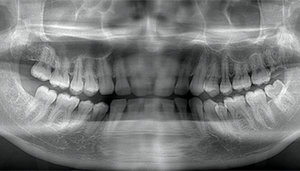

左下の歯茎が腫れている親知らずの症例

- 抜歯前写真(レントゲン、CT等)

左下の親知らず周囲歯肉が腫れていました。

また、手前の歯との間で虫歯もできていました。

3分割して抜歯しました。

| 年齢 | 20代・女性 |

|---|---|

| 主訴 | 左下の歯茎が腫れている |

| 適応するプラン | スタンダード親知らず抜歯プラン |

| 親知らずの生え方 | 歯茎から少し頭が出ている |

| 抜歯時間 | 15分 |

| 費用 | 約7,000円 |

| 抜歯内容 | 下顎の親知らずの抜歯希望の患者様です。 智歯周囲炎となっており、初診時では麻酔が効きづらい旨をお話しし、初診時は抗生物質をお出ししました。1週間後、ある程度歯肉の炎症がとれたことを確認して抜歯を行いました。 麻酔を行い、遠心(親知らずの奥側)歯肉と、手前の歯の頬側の歯肉を切開しました。 歯茎を開いて、手前の歯と引っかかっている部分をカットしました。 その後、骨からでている歯冠部(頭の部分)をカットしました。 その後へーベルで歯根(骨に埋まっている部分)を脱臼し、抜歯を終えました。 切開した歯茎を3針縫って、治療終了となりました。 歯茎を切ったため、3日ほど腫れぼったい感じがあったようですが、痛みはほとんどなく、治癒に向かいました。 |